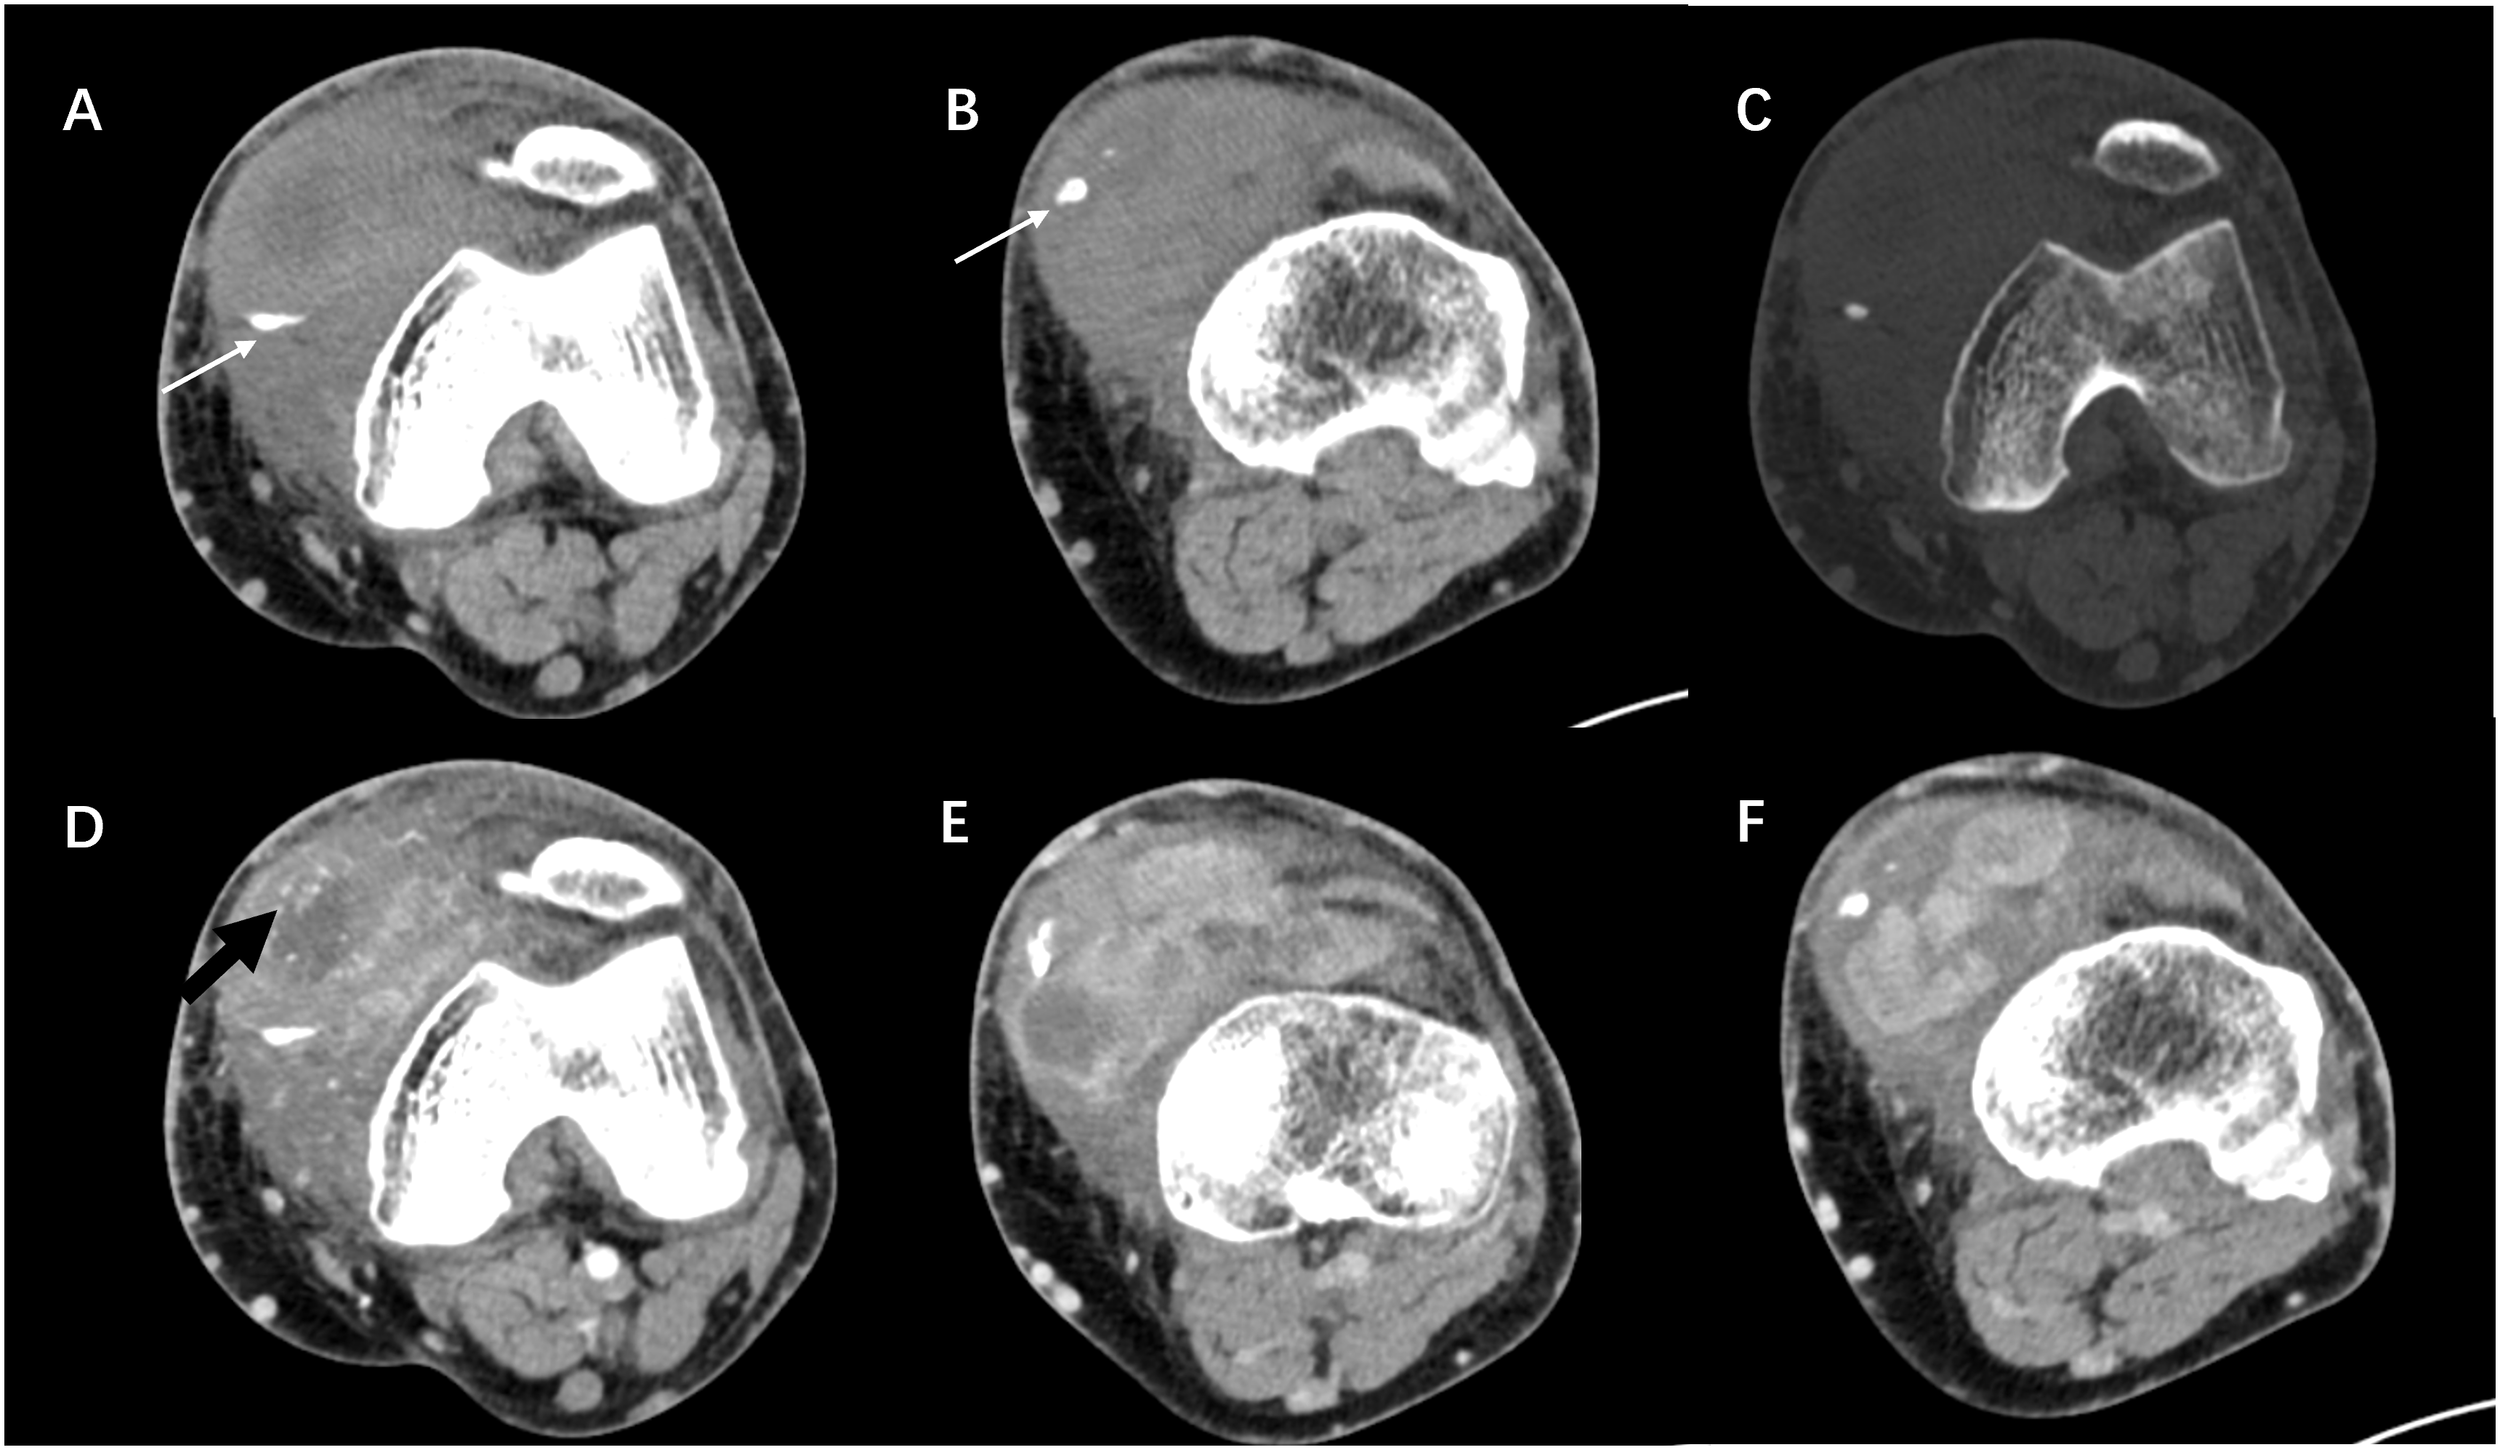

Figure 2

(A–C) Axial CT images showing a soft tissue mass in the anteromedial side of the left knee, which was irregular in shape and ill-defined in boundary, without bone destruction. The calcification was mainly located at the edge of the lesion (white arrow). (D–F) Contrast-enhanced scan showing the markedly heterogeneous enhancement of the mass. Nodular enhancement and enhanced vessels (black arrow) could be seen within the mass.